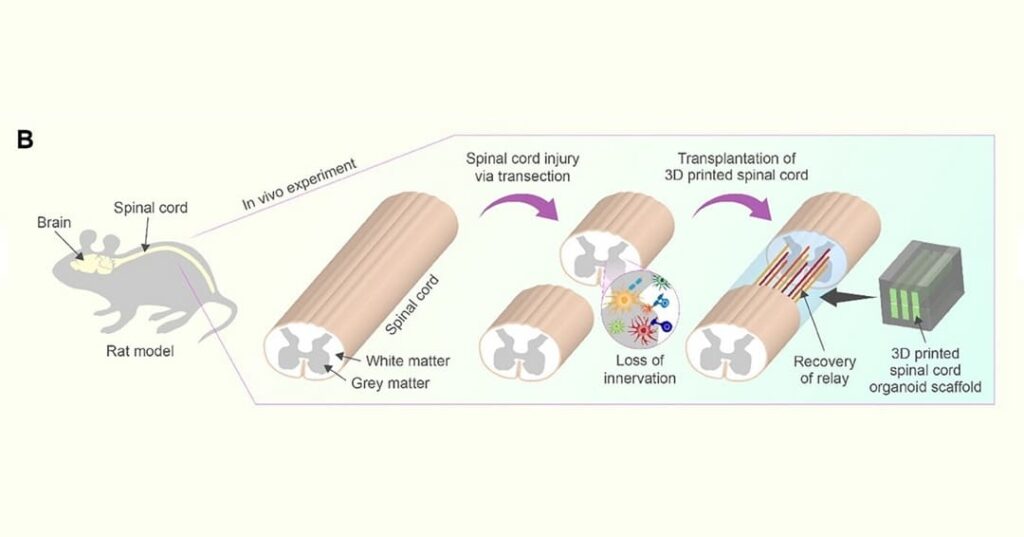

En el estudio —apoyado por los NIH, el Programa de Becas para la Investigación de Lesiones de Médula Espinal y Traumatismos Cerebrales de Minnesota, y la Sociedad de la Médula Espinal— los investigadores trasplantaron estas estructuras a ratas con la médula espinal completamente seccionada.

Las células se diferenciaron exitosamente en neuronas y extendieron sus fibras nerviosas en ambas direcciones —hacia la cabeza (rostral) y hacia la cola (caudal)— estableciendo nuevas conexiones con los circuitos nerviosos existentes del animal.

Con el tiempo, estas nuevas células nerviosas se integraron de manera completa en el tejido de la médula espinal, lo que resultó en una recuperación funcional notable en las ratas.